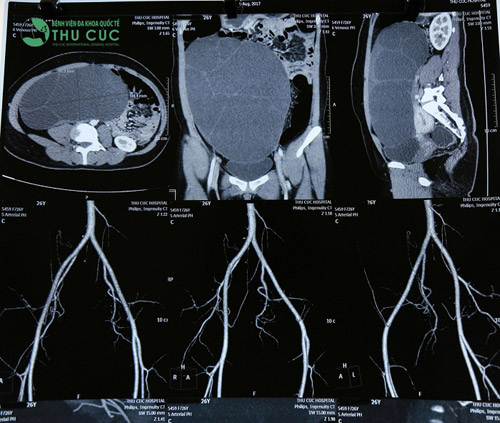

Qua thăm khám và thực hiện các xét nghiệm cần thiết, các bác sĩ của Bệnh viện Thu Cúc cho hay khối u nang buồng trứng trong cơ thể chị T có kích thước 25x20x10cm, u chiếm phần lớn ổ bụng và đè đẩy vào các tạng. Nếu không phẫu thuật sớm, u đe dọa vỡ, gây nguy hiểm cho tính mạng.

Hình ảnh khối u trong phim chụp.